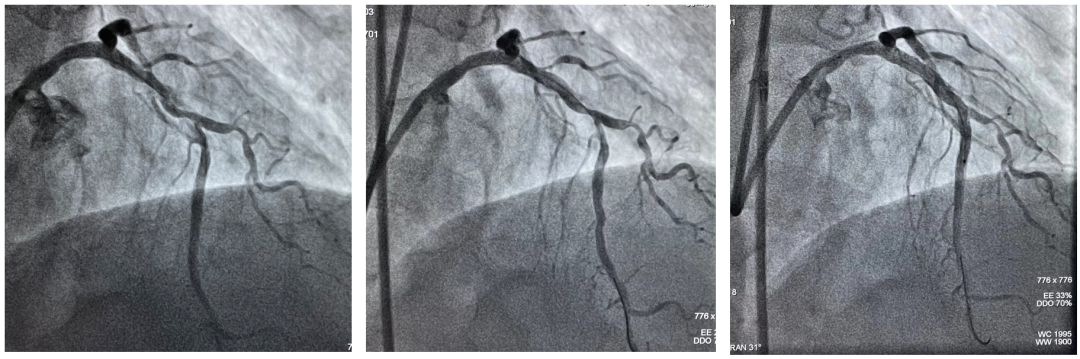

Shockwave球囊冲击波治疗冠状动脉钙化病灶前后造影及支架植入术后造影

延长导管支持下,3.0mmx12mm Shockwave冲击波球囊精准定位于前降支近段钙化最重处,先后触发60次脉冲冲击波(6个周期),实施钙化斑块碎裂术,对治疗段进行低压球囊扩张成形,随后通过OCT及冠脉造影融合技术证实,部分钙化病变得到松解,但中段成角病变处OCT提示仍有严重偏心钙化斑块,再次进行了20次脉冲冲击波(2个周期)治疗后,随着shockwave球囊能量的逐步释放,再次复查OCT显示原钙化环断裂,深层钙化碎裂。经过充分的冲击波球囊预处理,顺利完成进一步介入治疗。用时约40分钟,在患者无明显不适的情况下顺利完成介入治疗。术后患者顺利转入病房,并计划于近日出院。

Shockwave球囊冲击波治疗前后OCT成像对比

术前OCT(左)Shockwave球囊冲击波后(中)支架植入术后OCT(右)